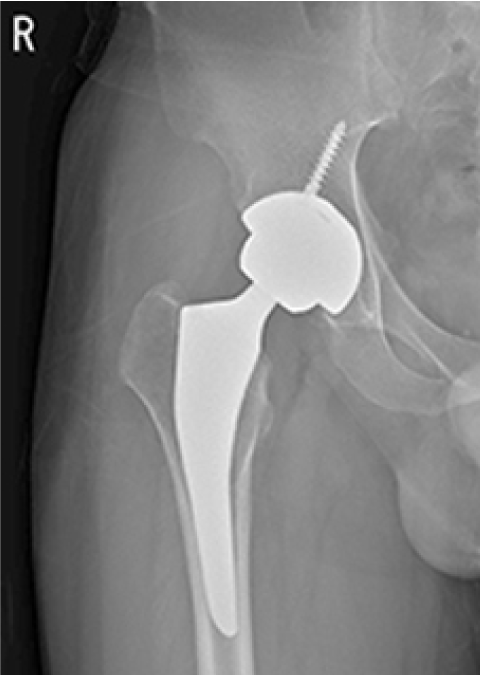

인공관절 수술 후

ㆍ환자 동의를 받은 자료이며, 이미지 사진은 실물과 다를 수 있습니다.

ㆍ2016.09.12(전) 2016.11.22(후)